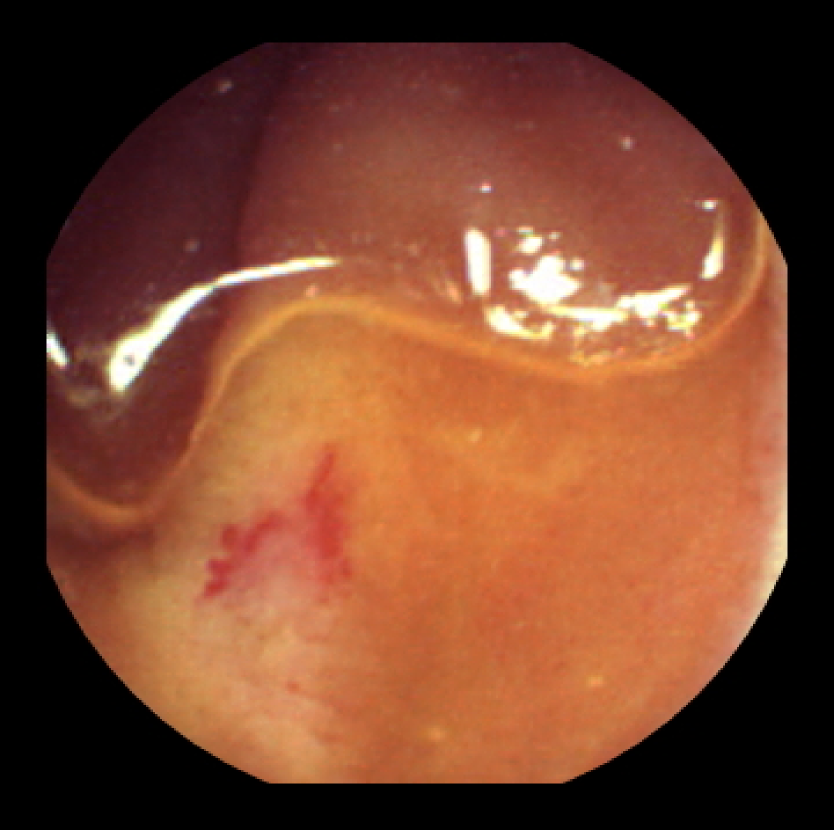

The RGB (Red, Green, Blue) endoscopic images are first converted into a colour space in which the components are de-correlated from the luminance component. Such colour spaces may include HSV (Hue, Saturation, Value) and CIELab colour spaces [5]. They are more near to the Human Vision System. The following figures show the colour transformation of an RGB endoscopic image to various colour components of the HSV and CIELab colour models.

(a) Original Image

Figure 1: Colour space transformation into HSV and CIELab